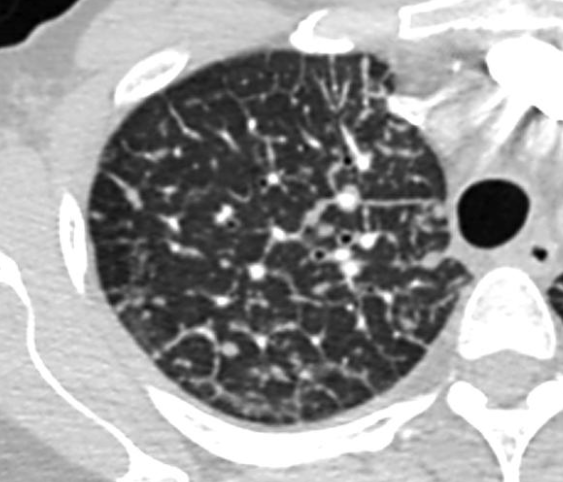

CT

- Epaississements irréguliers des septas

- Epaississements péri-bronchovasculaires